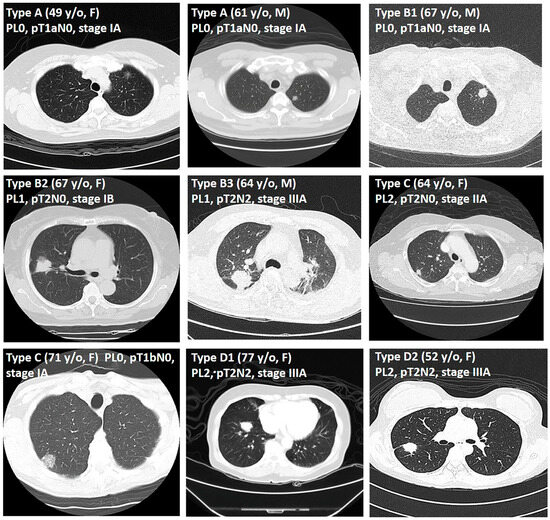

| 7 | Border type | 0.000 *** | |||

| A | 282 (43.9%) | 274 (49.3%) | 8 (9.2%) | ||

| B | 182 (28.3%) | 147 (26.4%) | 35 (40.2%) | ||

| C | 92 (14.3%) | 70 (12.6%) | 22 (25.3%) | ||

| D | 87 (13.5%) | 65 (11.7%) | 22 (25.3%) | ||